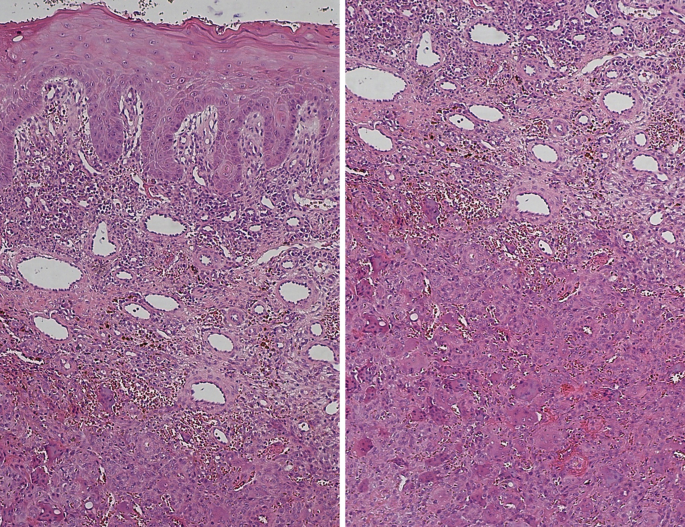

Peripheral Giant Cell Granuloma Histology

Histological appearance of peripheral giant cell granuloma ... Peripheral Giant Cell Granuloma : Giant Cell Epulis Pathology Outlines - Peripheral giant cell granuloma Rare Case of a Peripheral Giant Cell Granuloma of the Jaw as First ... Pathology Outlines - Peripheral giant cell granuloma Peripheral Giant Cell Granuloma Histology